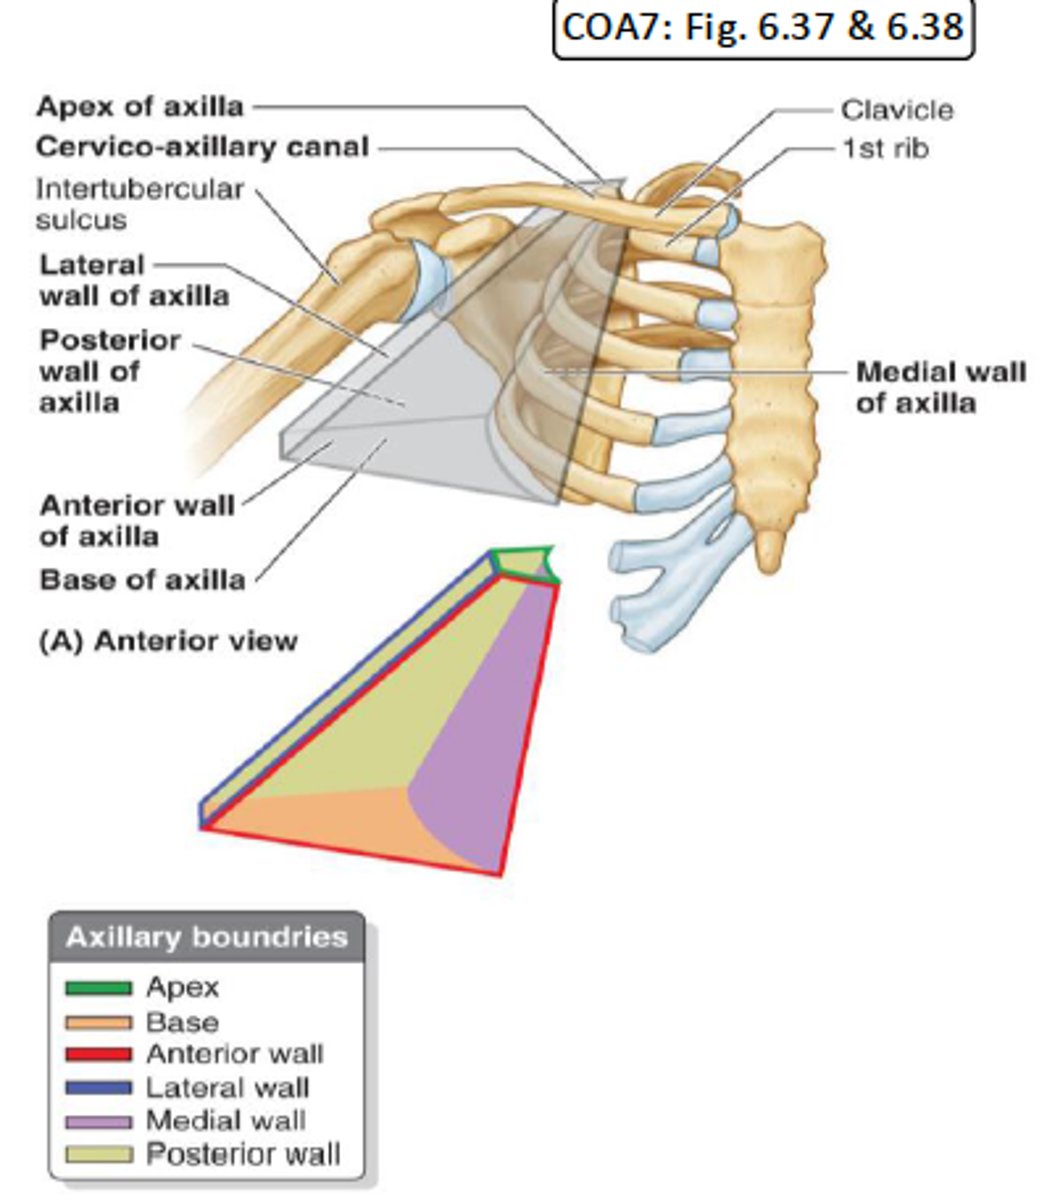

one of the boundaries of the cervico-axillary canal together with the scapula and 1st rib

What is the cervico-axillary canal?

passage between neck and arm

What does the cervico-axillary canal do?

protects the neurovascular bundle supplying the arm